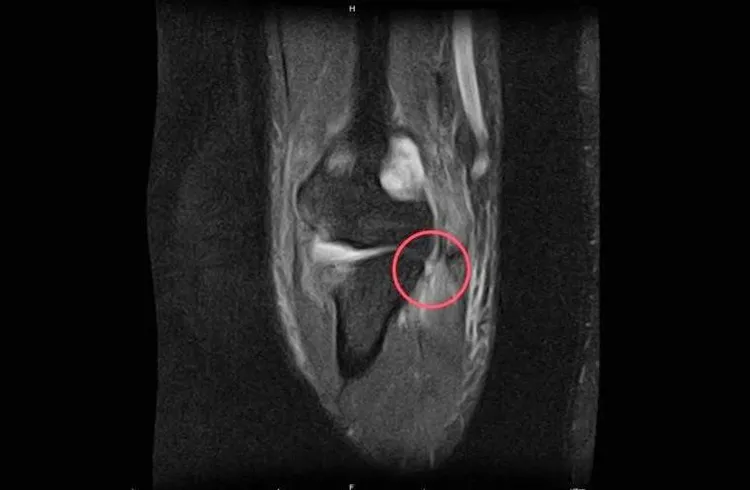

磁振造影下之尺側副韌帶斷裂處。院方提供

陳教授解釋,若是較輕微的尺側副韌帶損傷可以考慮先用石膏或肘支架固定的保守療法;而較嚴重複雜脫臼或伴隨骨折之病人則需進行手術作固定及韌帶修補。然而當治療失敗變成慢性的肘關節不穩定之病人,就得考慮施行手肘尺側副韌帶重建手術。